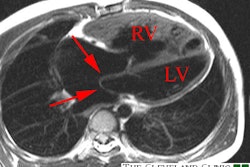

Infants typically present with failure to thrive, profuse sweating, dyspnea, and pallor [8]. The condition is one of the common causes of myocardial infarction and dilated cardiomyopathy in infants [7]. Without treatment, this anomaly most commonly results in death during early infancy (mortality rates of greater than 90% in the first year of life [7,15]), but survival into adulthood can occur if collateral coronary flow via the RCA is sufficient [8]. However, the risk for sudden cardiac death due to ischemic malignant ventricular dysrhythmia exits even in asymptomatic adult patients (sudden cardiac death occurs in 80-90% of cases) [5]. Treatment is surgical repair [5]- in infants this is done preferably using the coronary button transfer that produces the most anatomic correction and has excellent long-term results [8]. In adults, the preferred method is ligation of the LCA at its origin form the PA and placement of a CABG using the internal mammary artery or a saphenous vein graft [8]. In this syndrome, the LCA typically arises from the left inferolateral aspect of the main pulmonary artery just beyond the pulmonary valve [8].

Patients are generally noted to have an anterior wall ischemic perfusion defect and mitral insufficiency. An inferior/posterior perfusion defect may also be seen secondary to a right coronary artery to left coronary artery to pulmonary artery shunt.